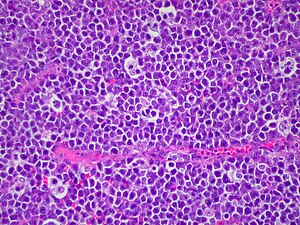

Starry-sky pattern. H&E stain.

LM medium-sized lymphoid cells of uniform size with abundant cytoplasm, interspersed macrophages

• "Starry-sky pattern":

• The stars in the pattern are: tingible-body macrophages.

• Tingible-body macrophages = macrophages containing apoptotic tumour cells.

• The tumour cells are the sky.

• Tumour cells:[2]

• Medium-sized (~1.5-2x the size of a RBC) with uniform size ("monotonous") -- key feature.

• Round nucleus.

• Small nucleoli.

• Relatively abundant cytoplasm.

• Brisk mitotic rate (near 100%).